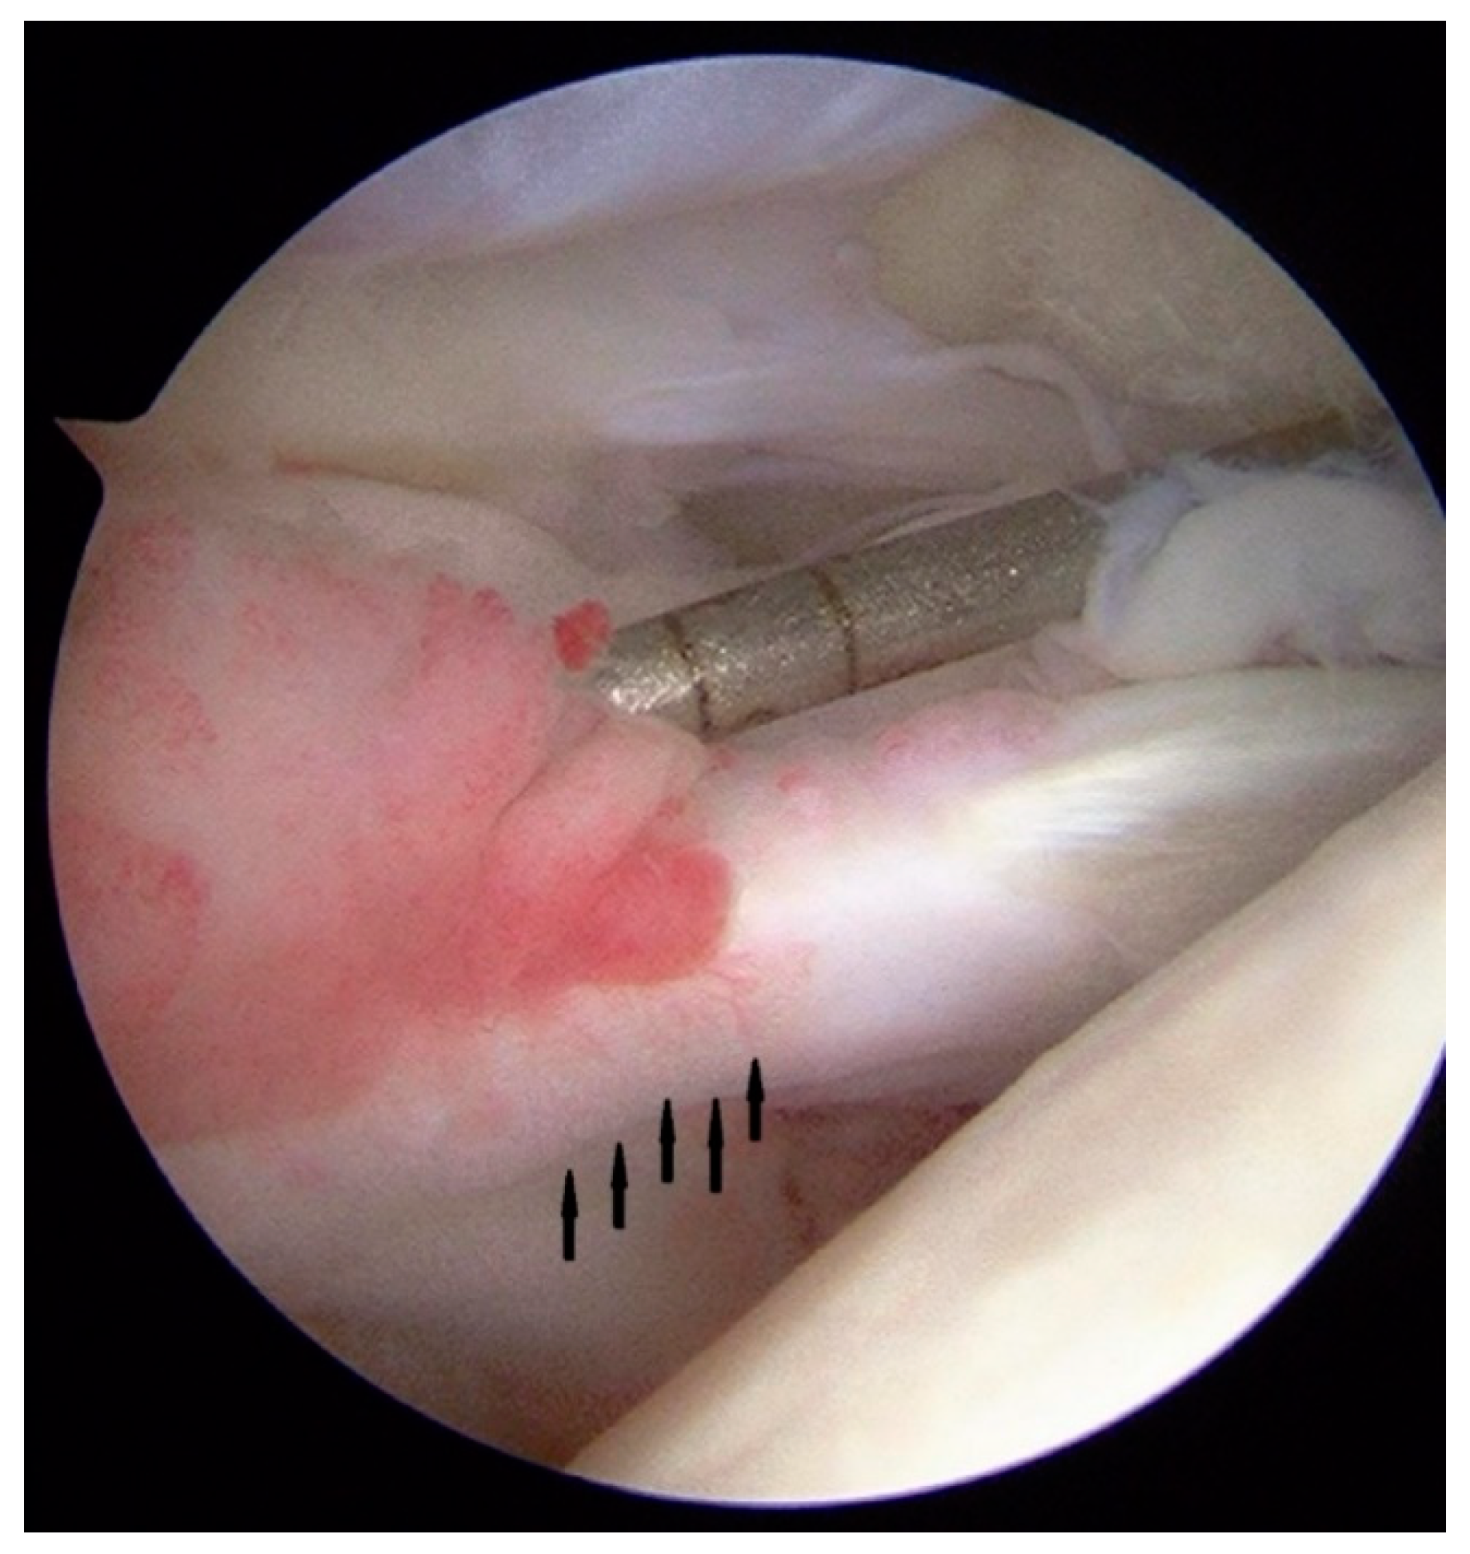

2. Neovascularization in Tendon Disorders and Its Therapeutic Potential

- Arnoczky, S.P.; Warren, R.F. Microvasculature of the human meniscus. Am. J. Sports Med. 1982, 10, 90–95. [Google Scholar] [CrossRef]

- Barber-Westin, S.D.; Noyes, F.R. Clinical Healing Rates of Meniscus Repairs of Tears in the Central-Third (Red-White) Zone. Arthrosc. J. Arthrosc. Relat. Surg. 2014, 30, 134–146. [Google Scholar] [CrossRef]

| Xue et al. [45] | Neovascularization was defined as vessel growth mainly at the adhesion margin for less than one-third of the meniscus body ransverse diameter. | Authors concluded that the revascularization after meniscus transplantation is very important to the healing process. Moreover, they found that no significant vascular distribution was found at the free margin of the meniscus. |